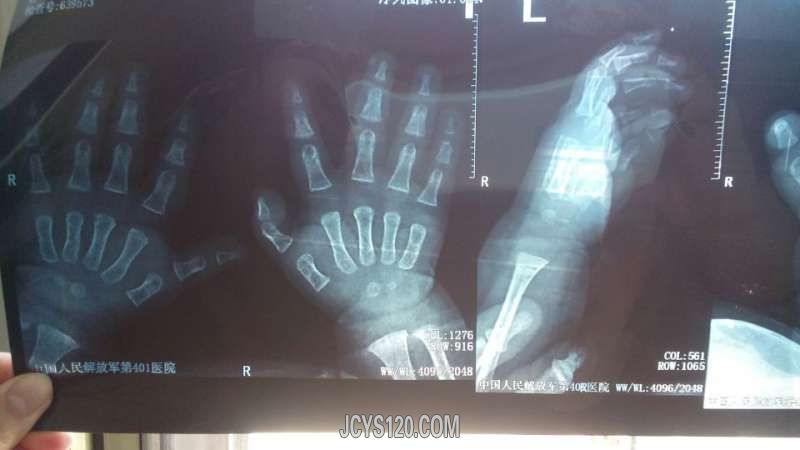

查体:体温37度 心率116次 ,发育正常,精神可,查体合作,颈部无抵抗,全身皮肤黏膜无黄染,无出血疹,浅表淋巴结无肿大,头颅五官无畸形,囟门未闭,双侧瞳孔等大等圆,对光反射好,双肺呼吸音正常,无痰鸣音,心脏不大,心音正常,无杂音,心率正常,全腹部无压痛及反射痛,腹软,无气过水声,肠鸣音正常,肝脾未触及,双下肢无水肿,生理反射存在,病理反射未引出。右侧大拇指无肿胀,不红没有淤血瘀斑,无触痛,大拇指明显弯曲,伸手指小儿不配合,其它手指均正常

小儿右手指正侧位片,大家看看小儿属于什么情况,其实我的诊断和市医院诊断一致!你的诊断?治疗?鉴别诊断?回答正确加分!